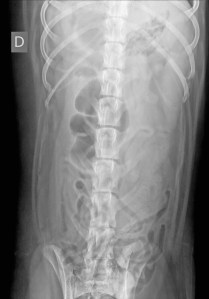

Signalement: Labrador croisé de 4 ans, mâle castré.

Histoire clinique: vomissements aigus.